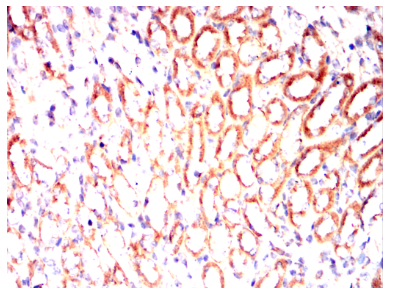

IHC    1/200 - 1/1000